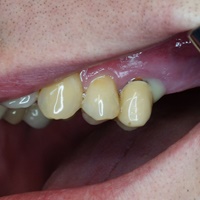

Dziesieć lat po wykonaniu mostu pacjent zgłosił się z recesją dziąsła i próchnicą korzenia. Zamiast ekstrakcji wykonano hemisekcję i nowy most.